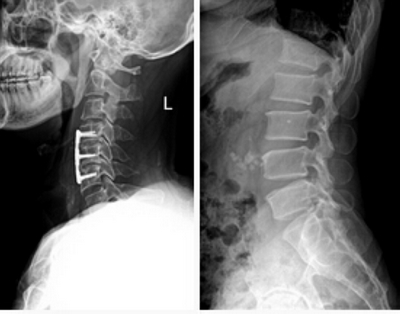

★適用于全身各部位攝影,包括常規(guī)攝影(立位攝影、臥位攝影等,如胸片、頸椎、腰椎、腹部、頭顱、四肢等)和特殊攝影(傾斜攝影、角度攝影等,如瓦氏位、骶髂關(guān)節(jié)、髕骨軸位、跟骨軸位等)。

★各種普通及特殊造影,如口服膽囊造影、靜脈膽道造影、T管造影、逆行胰膽管造影(ERCP)、靜脈腎盂造影(IVP)、子宮輸卵管造影、脊髓造影等。